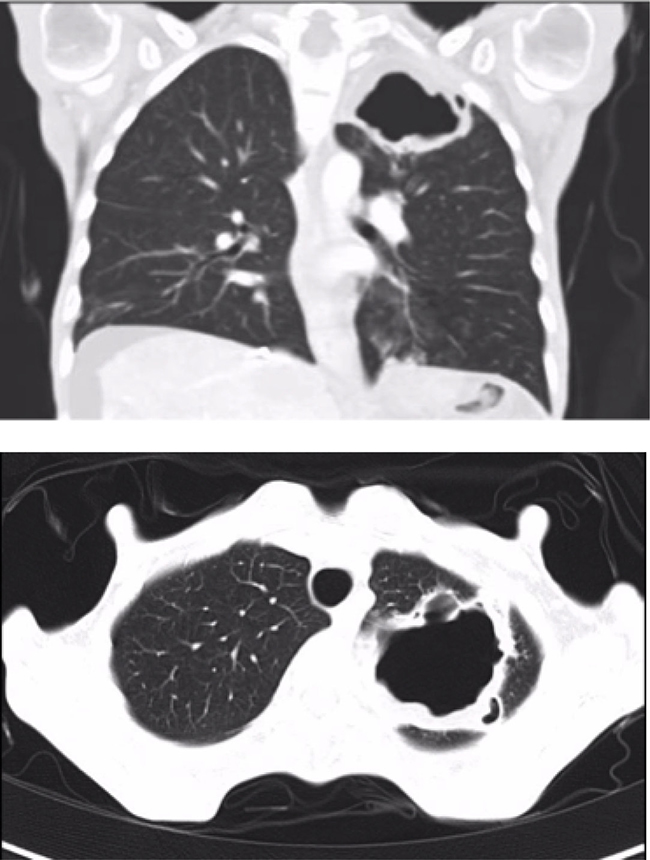

A 36-year-old woman had an invasive pancreatic neuroendocrine tumor removed by means of body and distal pancreatectomy, splenectomy, partial gastrectomy, and transversal colectomy. One-year later, multiple liver metastases were detected in both lobes. At that moment, she had chronic malnutrition despite adequate pancreatic enzyme supplementation and a Trousseau syndrome was also diagnosed. Chronic malnutrition was attributed to a combination of pancreatic insufficiency and a potential hormone-related paraneoplastic syndrome. Systemic chemotherapy with 5-fluorouracil and streptozotocin followed by transarterial bland embolization were performed, and an objective durable remission was achieved. Seven years later, liver progression was detected, restricted mostly to the right lobe. Her performance status was ECOG 1 but she had a BMI of 13.7 kg/m2 due to worsened chronic malnutrition. A left pleural effusion was also observed but no malignant cells were detected on fluid cytology. A right-lobe transarterial radioembolization (TARE) was uneventfully performed. The lung shunt fraction in the macroaggregated albumin scan performed during the TARE workup was 6.4%. The response to TARE was short lived and 9 months later liver disease progressed. The multidisciplinary team recommendation was to start Sorafenib as a special indication under informed consent instead of Sunitinib due to her profound asthenia. The dose used was progressively increased from 400 mg to 600 mg daily with good tolerability and no side effects. Two months later a thoracic CT showed a small pleural effusion in left side and ground glass in left lower lobe. Four months after initiating Sorafenib an abdominal and thoracic CT showed a lung cavity in the left upper lobe (Figure 1). The patient had no respiratory symptoms.

Figure 1: Pneumatocele in the upper left lobe (55 × 38 × 44 mm) (Case 1).